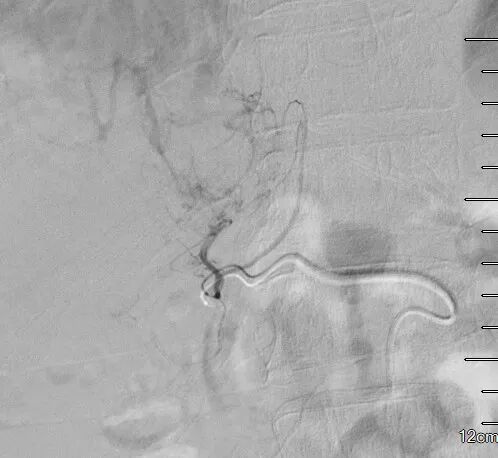

手术过程

术中造影发现肿瘤巨大,染色明显,微导管超选至其中几支肿瘤供血动脉后,予表柔比星80mg+聚乙烯醇栓塞微球(蓝色型,100-300um)、5支无色型(300-500um),1支无色型(500-700um)栓塞肿瘤供血动脉,直到栓塞至肿瘤血管血流停滞。